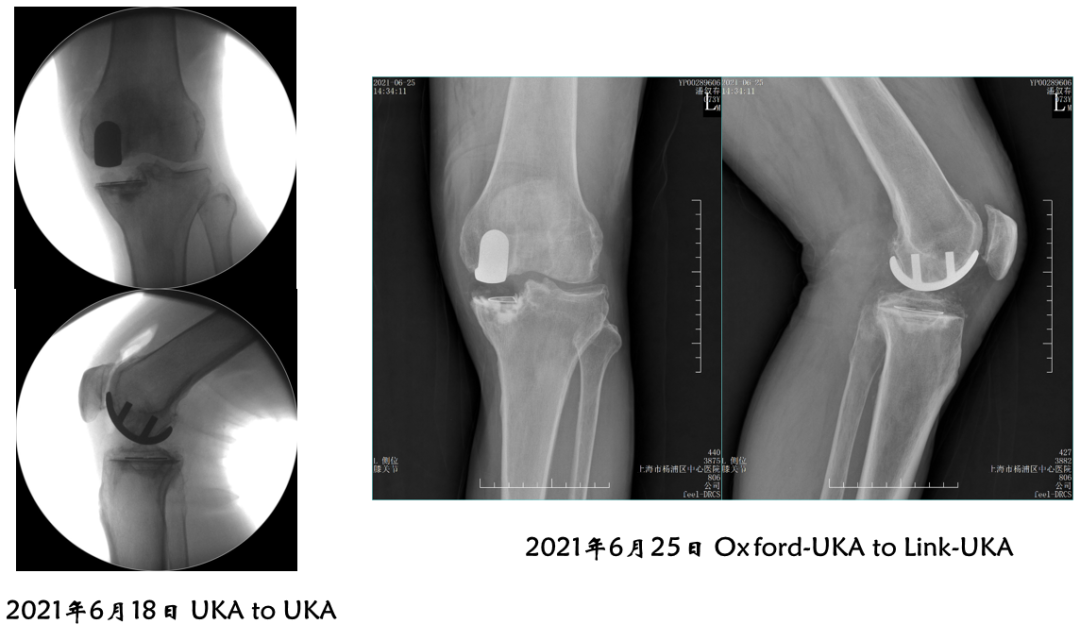

病例4:内侧OxfordUKA术后6.5年外侧进展性OA

病例4:Bi-UKA术后

病例4:Bi-UKA术后Bearing 后脱位的处理